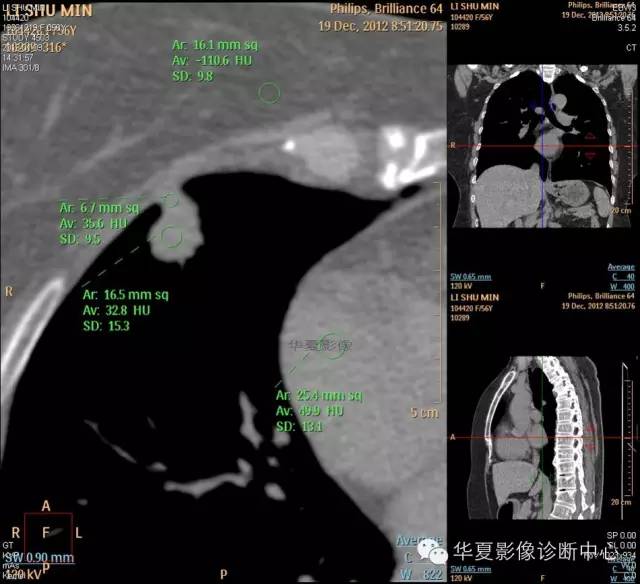

1.右肺上叶:肺组织1块,大小13×4×7cm。切面棕红色。2.右肺上叶肿物:灰白色组织一块,大小3×1×1.5cm。切面灰白色。3.右肺中叶结节:灰白色绿豆大组织1块。4.淋巴结:灰黑色绿豆大组织1块。

检查结论:

(右)肺中分化鳞状细胞癌。浸及胸膜。支气管残端切净。淋巴结未见癌转移(0/10)。